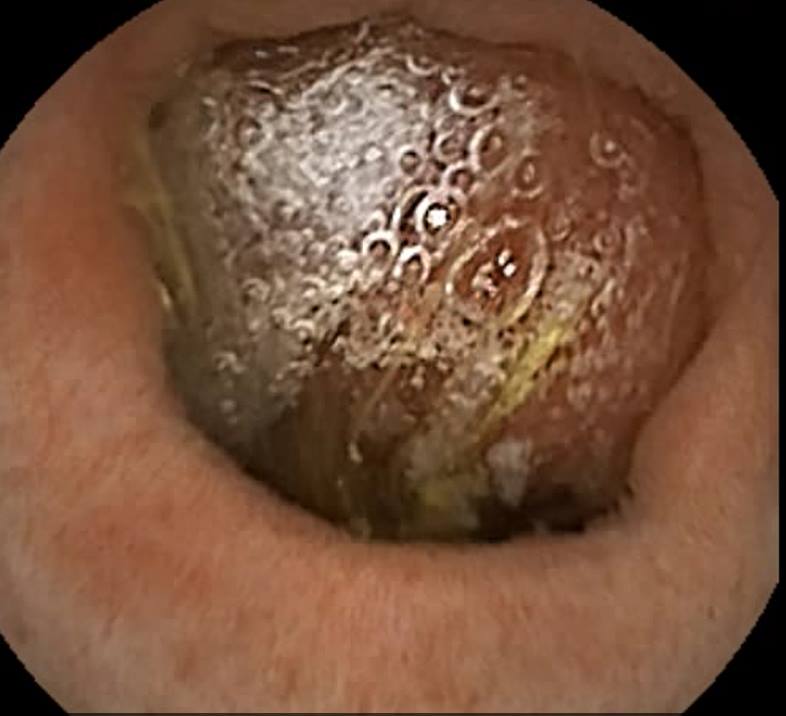

Capsule Endoscopy: Gastric Antral Vascular Ectasia (GAVE)